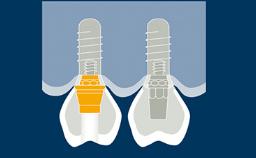

Prosthodontic Planning Principles for Implant Placement

Regardless of the location or extent of treatment, the planning of implant therapy should always be prosthodontically driven.

This ensures that the implant placement will serve the needs of the prostheses and will be compatible with the desired end result.

With the aim of achieving an optimal outcome, the prosthodontic planning should include consideration of all relevant prosthodontic factors and an appropriate diagnostic work-up as the basis for the specific planning of implant prostheses and supporting implants.